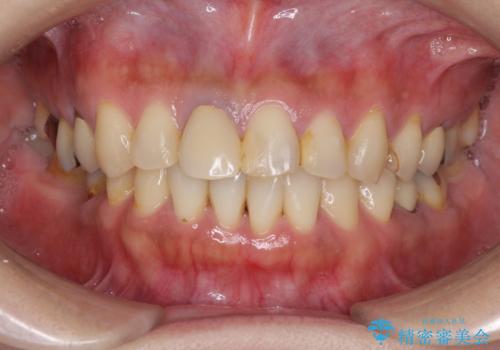

- 右下の欠損部の治療を希望して来院された患者様です。

部分矯正を行った後にインプラント埋入と手前の歯の根管治療を行い、その後補綴治療を行うこととしました。

治療途中より、上の歯や反対側の銀歯、上顎前歯の色合いや下顎前歯のデコボコが気になってきたため、全てを治療することとしました。